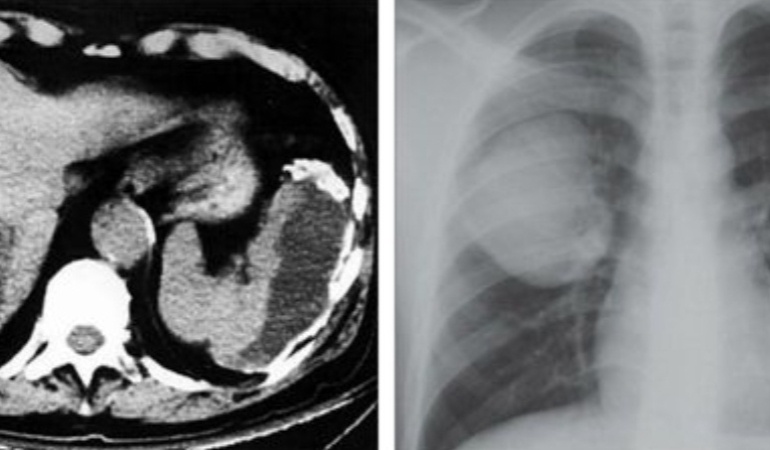

В одну из новгородских больниц обратилась женщина с результатами рентгена органов грудной клетки. На снимке были видны образования в лёгких размером с яблоко:

справа – 76х66х66 миллиметров, слева81х69х70 миллиметров. Больная – уроженка республики Таджикистан, длительное время занималась передержкой собак. Никаких симптомов пациентка не чувствовала.

На рентгене было выявлено наличие воздуха и избытка жидкости в плевральной полости, а также заподозрен прорыв кисты.